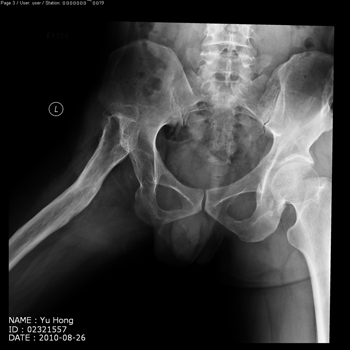

total hip replacement on hips with unilateral severe dysplasia and high riding